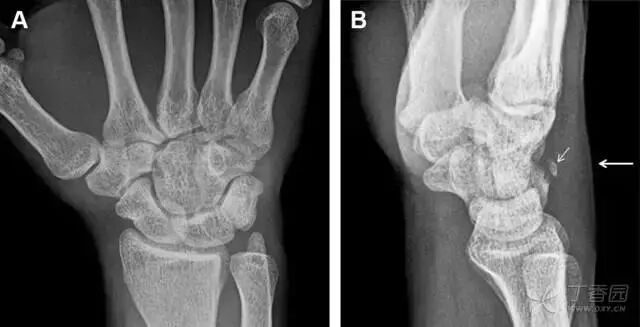

30桡骨远端骨折

常规进行前后位、侧位、斜位 X 线检查,对于大多数桡骨远端骨折来说不容易漏诊;但是对于无移位的骨折,特别是桡骨茎突骨折,容易漏诊。桡骨茎突骨折是一斜行的骨折,常累及关节面,常发生于轴向应力或直接打击。

图 1 57 岁女性,摔倒后手掌撑地,桡骨茎突压痛。(A~C)前后位、斜位、侧位片示软组织肿胀(*)和发丝样骨折(白色箭头);(D~F)2 周后,前后位、斜位、侧位片示骨折线显明,由于新骨痂沉积而呈现透亮线与硬化线并存;(G~I)另一患者,桡骨茎突骨折在前后位及侧位片上显示不明显,而在斜位片显示更清楚